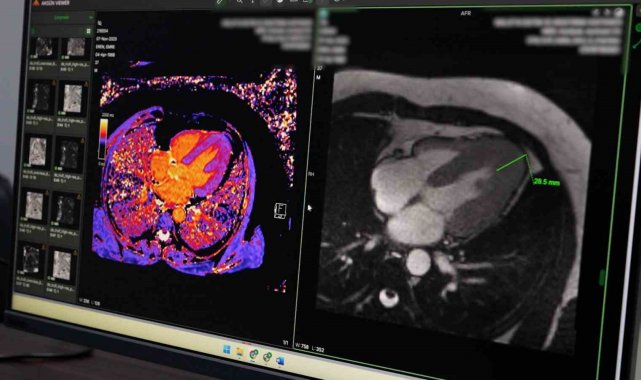

Hastanede uygulanan koroner BT anjiyografi yöntemiyle kalp damarlarının girişimsel işleme gerek kalmadan görüntülenebildiğini belirten Petik, bu sayede hastaların klasik anjiyografi öncesinde detaylı şekilde değerlendirilebildiğini ifade etti. Yeni başlatılan kardiyak MR uygulamasının da kalp kası ve kapak hastalıklarının tanısında önemli katkı sunduğunu dile getirdi.

Örnek bir vakaya da değinen Petik, kardiyak MR sayesinde nadir görülen bir kalp kası hastalığının erken dönemde tespit edilerek hastaya uygun tedavi planlamasının yapıldığını ifade etti. Petik, yapılan yatırımlar ve güçlü teknik altyapıyla Malatya Eğitim ve Araştırma Hastanesi'nin ileri görüntüleme alanında bölgesel merkez olma yolunda önemli mesafe kat ettiğini belirterek, vatandaşların başka illere gitmeden nitelikli sağlık hizmetine ulaşmasının hedeflendiğini söyledi.